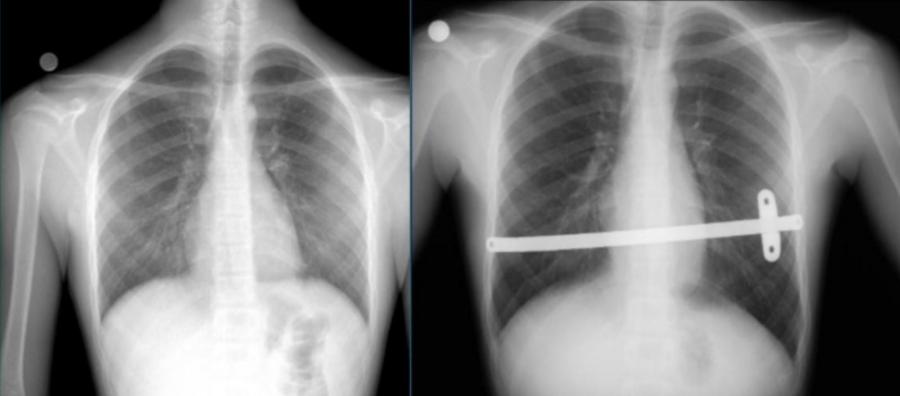

Kunduracı göğsü tedavisinde günümüzde Nuss yöntemi dediğimiz kapalı kamera yardımı ile çökük olan kısmın altından çelik veya titanyumdan üretilmiş bar denilen malzemenin konulması ile yapılır.

Nuss yöntemi, kamera eşliğinde kapalı olarak yapılan minimal invaziv ameliyat tekniğidir. Bu yöntemin daha kısa ameliyat süresi, estetik küçük ameliyat izleri, daha kısa hastanede kalış süresi ve ameliyat sonrası yüksek hasta konforu gibi avantajları bulunmaktadır.